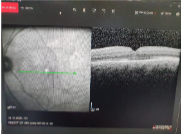

Makula deliği şikayetleri ile başvuran hastada ilk önce yapmamız gereken hastanın görme keskinliğine bakıp ayrıntılı reina muayenesi yapmaktir. Eğer delikten şüphelenirsek teşhiste altın standart ve %100 tanı koydurucu tek test OCT dir. OCT ağrısız ve boyasız noninvaziv bir yöntem olup hastalığın teşhisınde tek yöntemdir.

Resim 1: Bu resimde kliniğimizdeki 70 yaşındaki bir bayan hastaya ait makula deliğinin OCT görüntüsü görülmektedir. Hastamızın görmesi %1 olup şikayetleri 3 aydan beri devam etmekteydi.